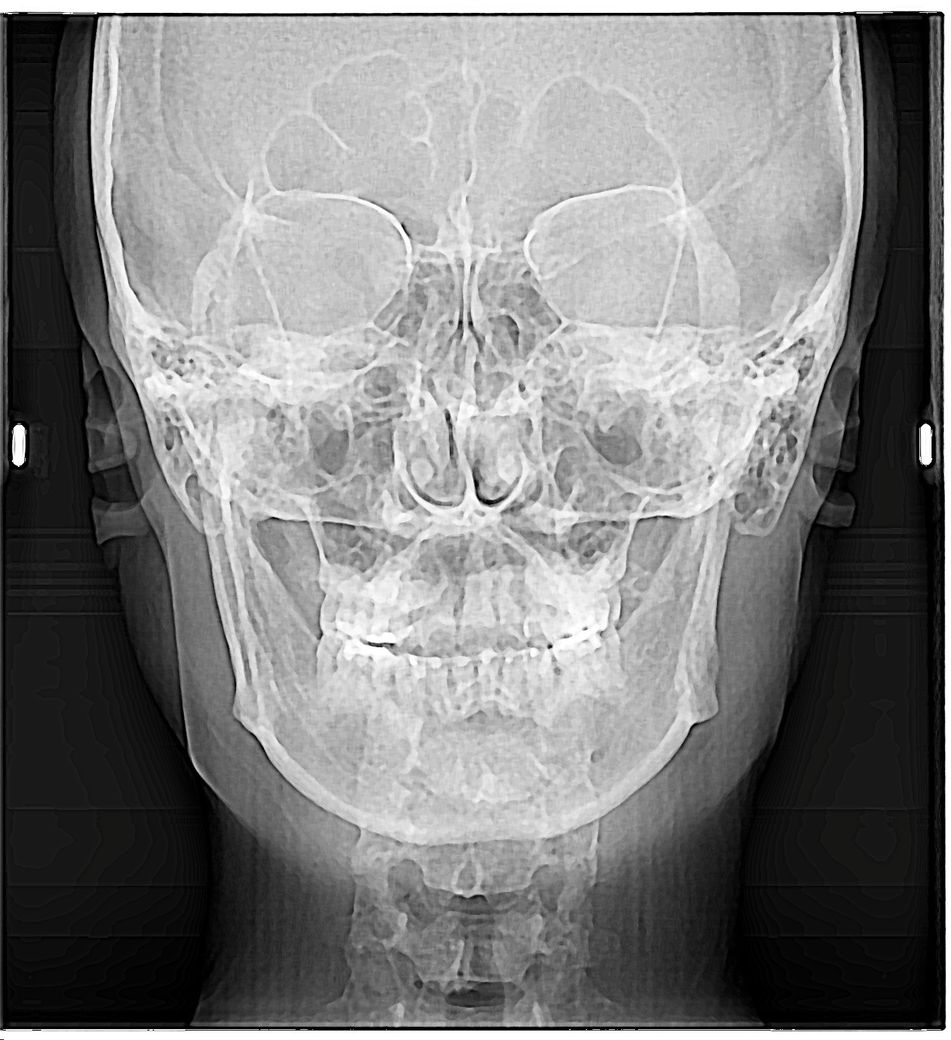

그리고 재교정 치아교정 받았고 밑에사진 오른쪽위 송곳니 자이 한칸씩 당겨서 교정했고 왼쪽 교합점이 높고 오른쪽이 낮은느낌.

• 3번 째 사진